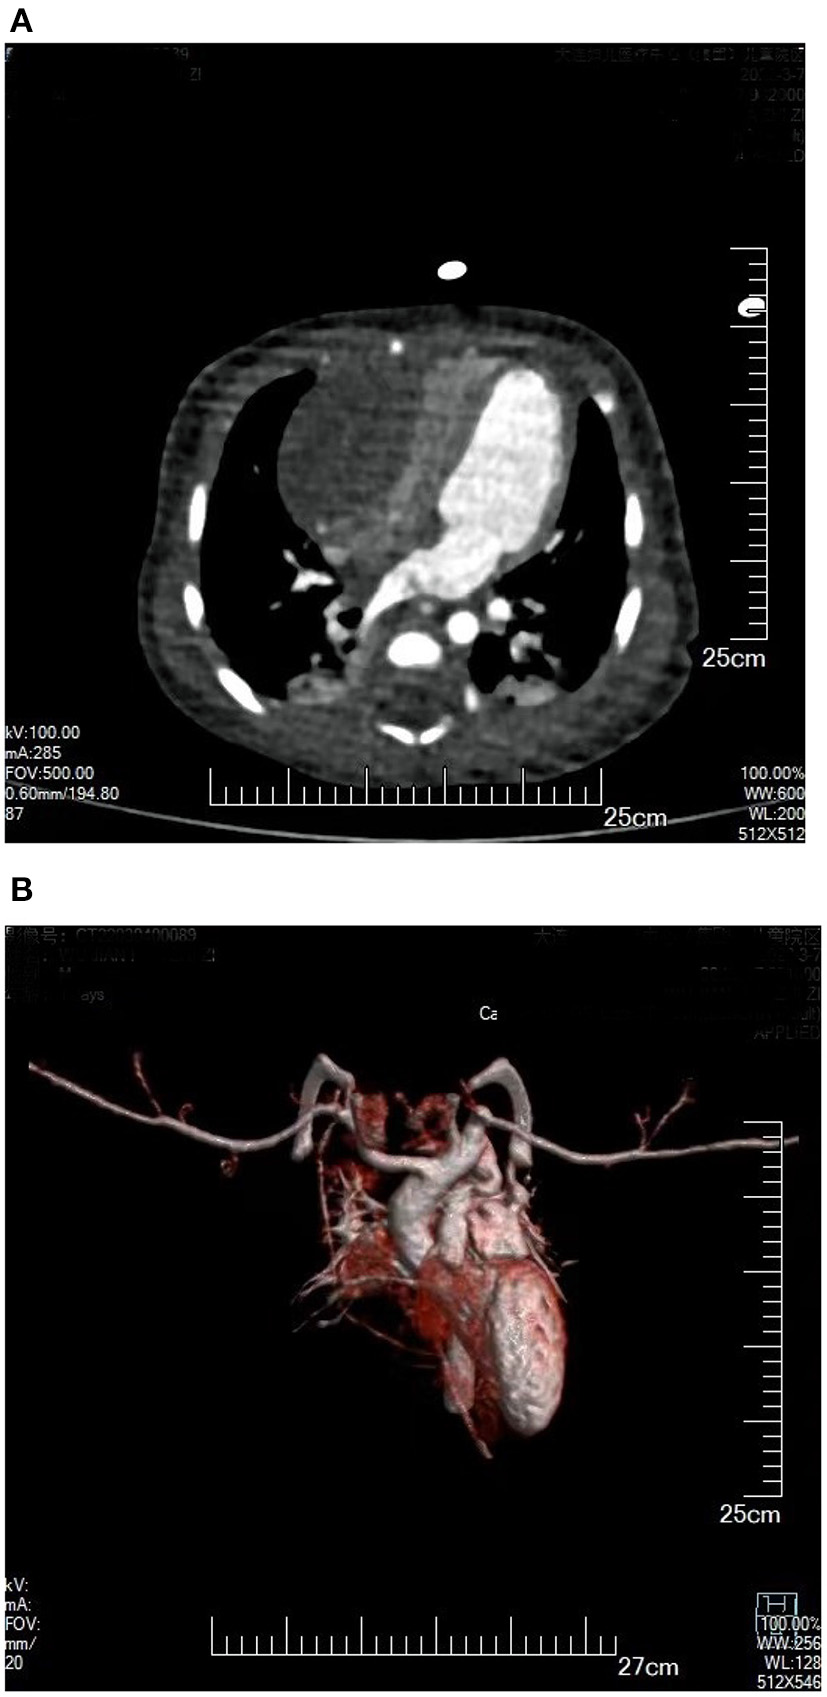

Figure 2

(A) Plain CT scan: Enormous space-occupying mass on a right ventricular wall, with compressed right ventricle cavity. (B) 3D reconstruction of cardiac blood flow: The right ventricular inflow tract was compressed by tumor, without obvious blood flow filling.

The study protocol was approved by the Dalian Women and Children's Medical Center (Group) Institutional Ethics Committee. The legal guardian signed informed consent for the operation and clinical record review. The patient is a test-tube baby, which means that the baby was a result of in-vitro fertilization. Fetal cardiac uhrasonography showed solid mass occupying the right ventricular wall and pericardial effusion; therefore, the patient was transferred to Cardiac care unit (CCU) after birth, early vital signs were stable and physical examination showed no obvious abnormalities. Cardiac uhrasonography: A hypoechoic mass of about 36 mm × 23 mm on the right ventricular wall, narrowing of the right ventricular inflow tract (Figure 1), a small amount of pericardial effusion, patent foramen ovale (2 mm), and patent ductus arteriosus (2 mm). Cardiac CT angiography (CTA): An elliptical low-density shadow of 35 mm × 23 mm on the right ventricular wall, with the right ventricle compressed (Figures 2A,B). The patient gradually had shortness of breath, rapid heart rate and oliguria, and cardiac echocardiography indicated increased pericardial effusion during observation. Tumor excision and ligation of ductus arteriosus were performed on Day 6 after birth. During the operation, the tumor was found to be yellow and hard, with a clear boundary with the myocardial tissue. Part of the myocardial tissue was enlarged along the boundary between the tumor and the myocardial tissue, and the marginal myocardial tissue was cut from multiple locations for pathological examination to ensure complete tumor resection, the fibroma was completely removed (Figures 3A–C), and the right ventricular wall wound was directly sutured. After the first cardiopulmonary bypass, the patient had severe hypotension and hypoxemia, making the condition unsustainable. The cardiopulmonary bypass was arranged again; given severe damage to the right ventricular wall due to tumor excision, and right heart failure, the ductus arteriosus was opened, the foramen ovale was enlarged, and various vascular drugs such as dopamine, adrenaline and prostaglandin were given; the patient was barely out of cardiopulmonary bypass, and transferred to the ICU with delayed sternal closure. The patient's vital signs were gradually stable, the chest was closed on Day 3, the respirator was removed on Day 6, and the patient was discharged on Day 14 after an operation. At present, the heart function has returned to normal, with a satisfactory prognosis. Pathologic results confirmed the presence of fibroma (Figures 4A,B).